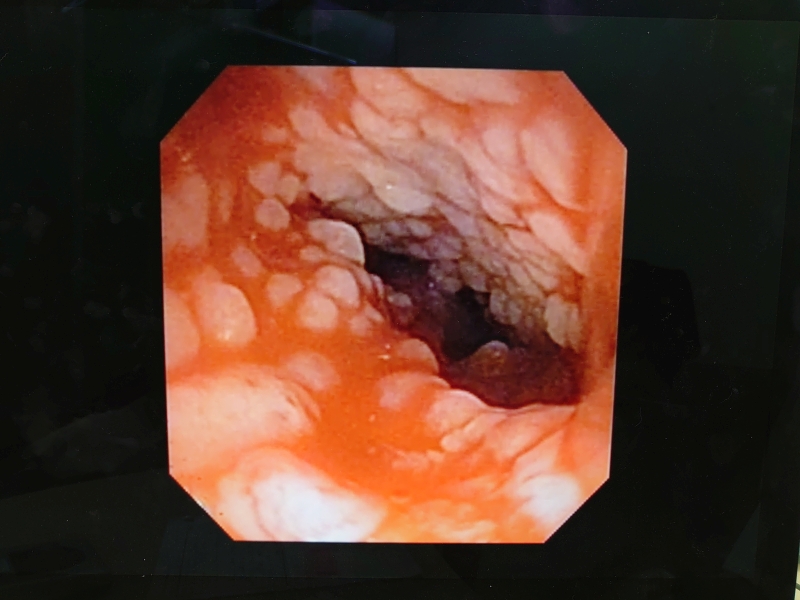

先生からCTと内視鏡の映像を見せてもらった

鼻咽頭内にぼこぼこしたものがへばりついてる..

確かに先日見せてもらったワンちゃんの狭窄とは異なり、空洞は広いようだけど何かがへばりついてる..

思わず「うわっ💦」って声が出た

先生が言っていた「ぼこぼこしたもの」は、この白いぼこぼこのことだった

鼻咽頭内は膿とか血液とか鼻汁とかはなく、ただぼこぼこしたものが覆い尽くしている..

先生の所見では今のところこれが炎症によるものなのか、リンパ腫なのかは判断できないとのこと..